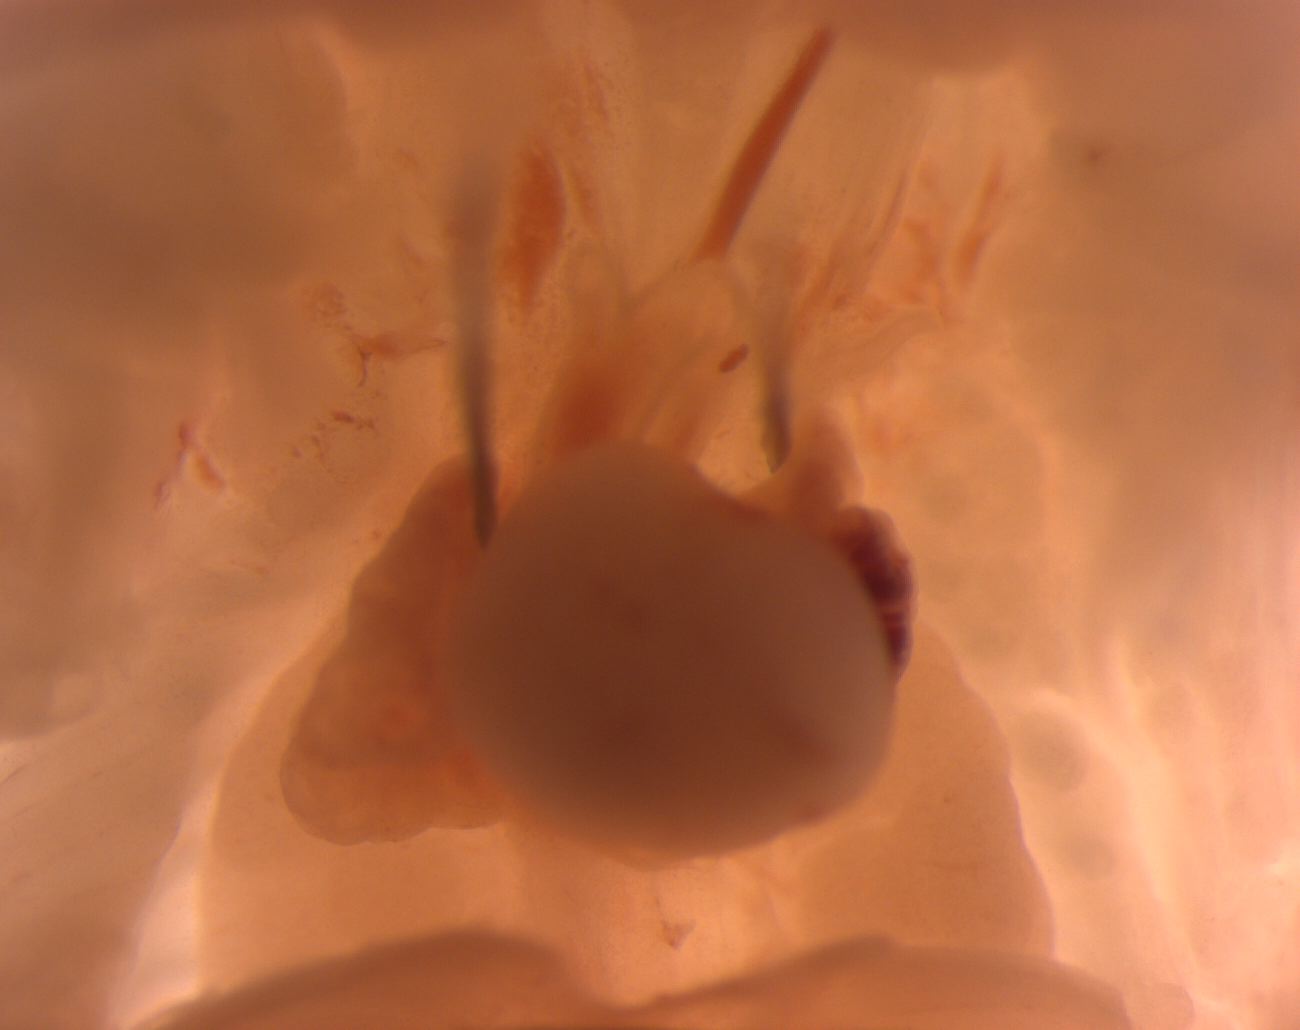

Caption Mutant 3260-003-3 (E17.5) exhibits abnormal arrangement of the outflow tracts which is diagnosed as an overridng aorta, AVSD, hypoplastic pulmonary artery, an aberrant right subclavian artery forming an incomplete vascular ring, and a tracheoesophageal fistula by histopathology.

Copyright This image is from the Laboratory of Dr. Cecilia Lo, a member of the Cardiovascular Development Consortium (CvDC), Bench to Bassinet (B2B) program of the National Heart Lung and Blood Institute (NHLBI), and is displayed with the permission of the authors. J:175213